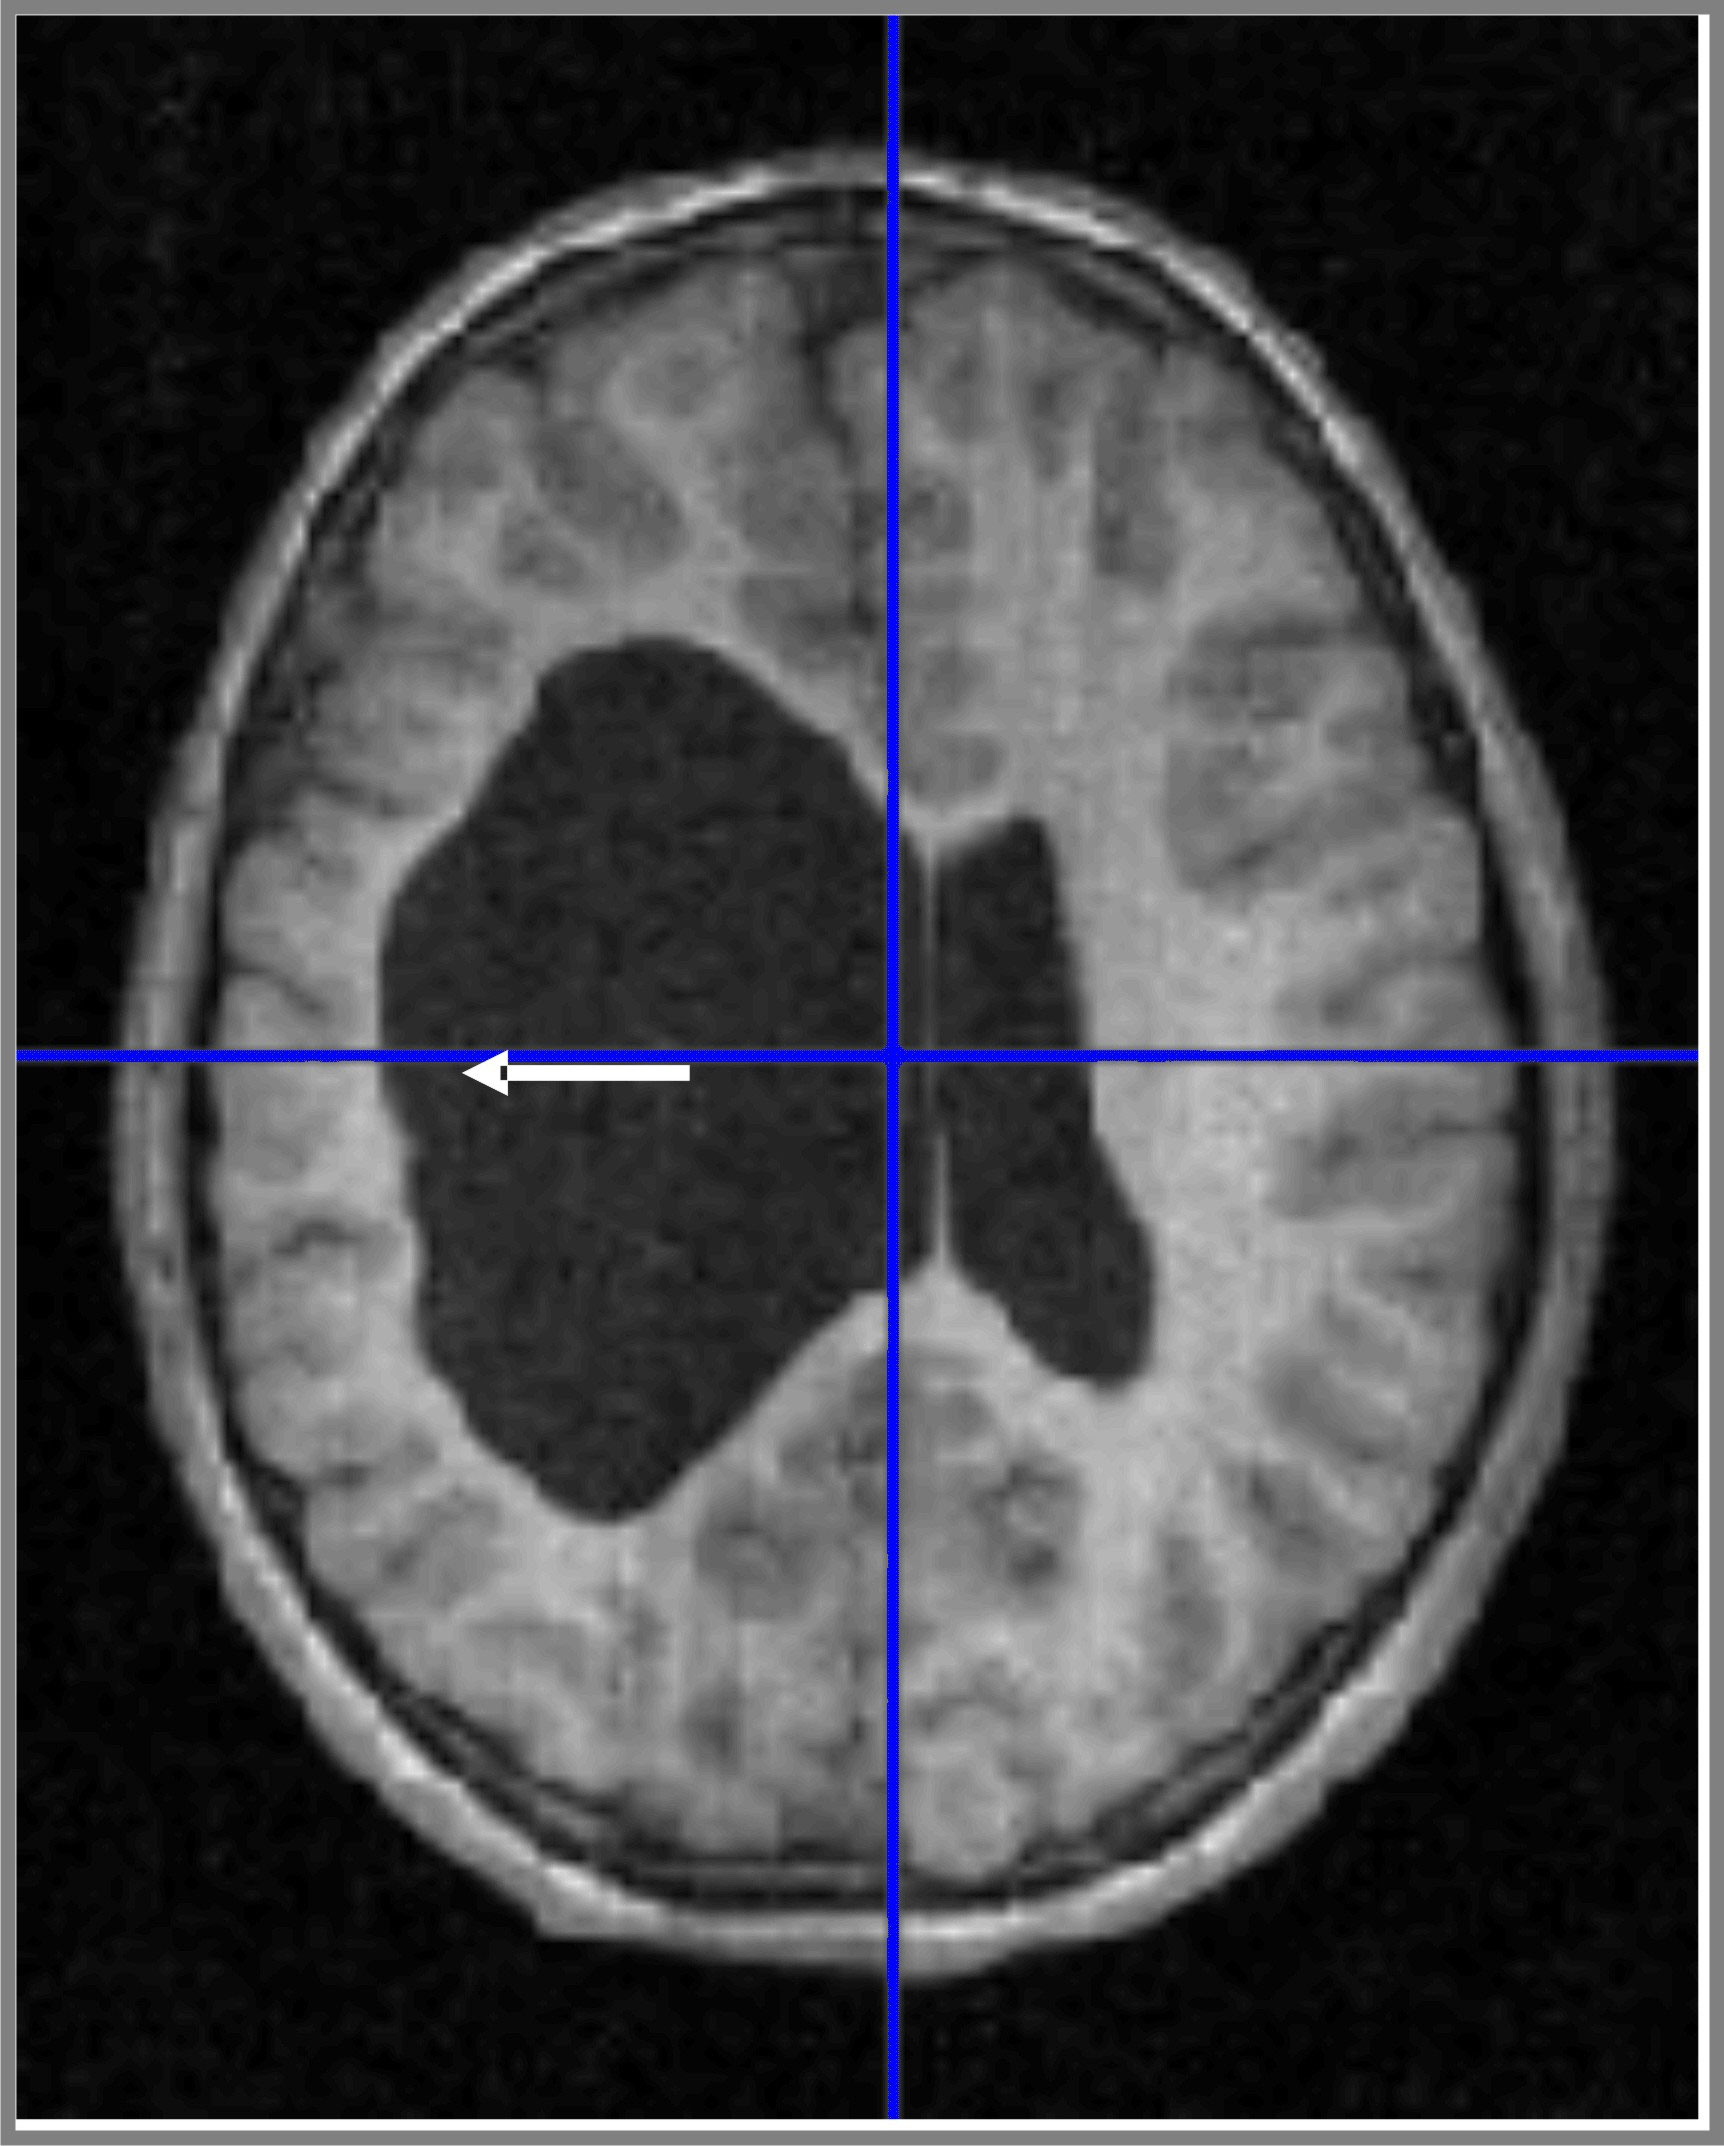

Wenn wir von einer Marklagerläsion sprechen bedeutet das, dass Ihr Hirn an genau dieser bestimmten Stelle stark, leicht oder mittelschwer beschädigt ist Wie ernst sind Hirnläsionen und wie werden sie behandelt? Hier finden Sie Informationen über diese verwirrend und beunruhigend Gesundheit

Wenn wir von einer Marklagerläsion sprechen bedeutet das, dass Ihr Hirn an genau dieser bestimmten Stelle stark, leicht oder mittelschwer beschädigt ist Eine Hirnläsion ist eine Art Anomalie im Gehirn , die normalerweise durch eine Krankheit oder Verletzung verursacht wird 1 Was ist eine Läsion? 2 Ursachen 3 Wann zum Arzt? 4 Symptome und Verlauf 5 Diagnose 6 Komplikationen 7 Behandlung und Therapie 8 Aussicht und Prognose 9 Quellen

SLAP Läsion Was ist das? Was kann man dagegen machen? Operation und Physio. Wie ernst sind Hirnläsionen und wie werden sie behandelt? Hier finden Sie Informationen über diese verwirrend und beunruhigend Gesundheit Die Symptome einer Hirnläsion sind vielfältig und hängen stark von der Lage und Größe der Läsion ab.